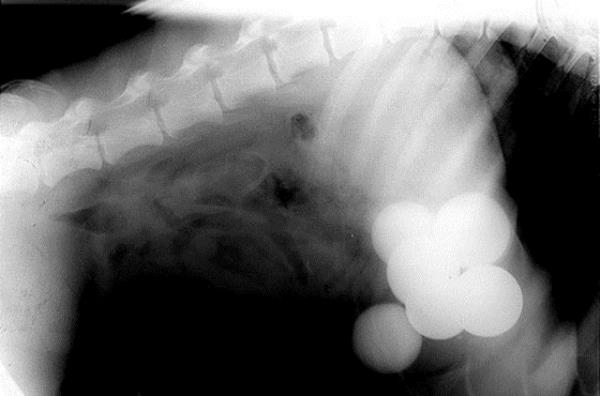

16. Doberman cinsi bu köpeğin röntgeninde ise midesinde altı tane golf topu var.

Doberman cinsi bu köpeğin röntgeninde ise midesinde altı tane golf topu var.